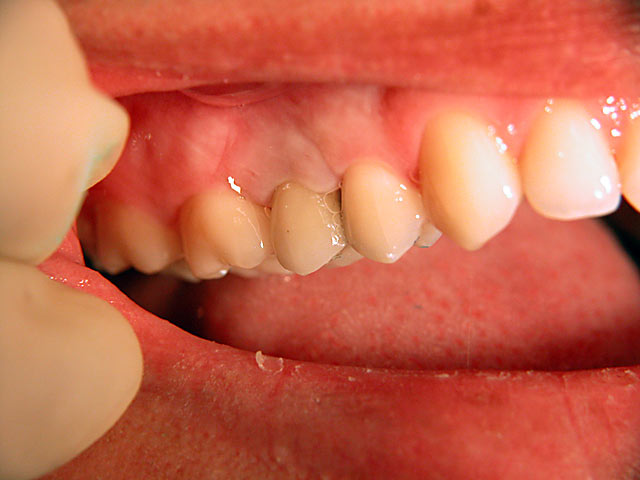

Implantation – Patientenbeispiel 1: